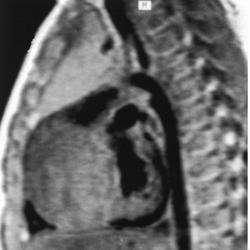

Фиброма может располагаться в разных отделах сердца, наиболее часто - в желудочках или межжелудочковой перегородке. Как правило, она представляет собой солитарное образование диаметром 3-10 см плотной консистенции, имеющее серовато-белую окраску (рис. 65). Опухоль четко отграничена от окружающих тканей, но не имеет капРис. 65. ЭхоКГ фибромы ЛЖ (парастернальная позиция по длинной оси; В-режим) сулы, характеризуется инвазивным ростом. При микроскопическом исследовании центральная часть опухоли состоит из гиалинизирован-ной фиброзной ткани с множественными очагами кальциноза и кис-тозной дегенерации, на периферии находятся веретенообразные клетки типа фибробластов с зернистой цитоплазмой и овальными ядрами с 1-2 ядрышками. Клетки располагаются между пучками коллагеновых волокон, имеющих различное направление.